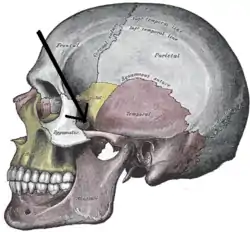

In anatomy, the zygomatic arch, or cheek bone, is a part of the skull formed by the zygomatic process of the temporal bone (a bone extending forward from the side of the skull, over the opening of the ear) and the temporal process of the zygomatic bone (the side of the cheekbone), the two being united by an oblique suture (the zygomaticotemporal suture);[1] the tendon of the temporal muscle passes medial to (i.e. through the middle of) the arch, to gain insertion into the coronoid process of the mandible (jawbone).

The jugal point is the point at the anterior (towards face) end of the upper border of the zygomatic arch where the masseteric and maxillary edges meet at an angle, and where it meets the process of the zygomatic bone.

Structure

The zygomatic process of the temporal arises by two roots:

- an anterior, directed inward in front of the mandibular fossa, where it expands to form the articular tubercle.

- a posterior, which runs backward above the external acoustic meatus and is continuous with the supramastoid crest.

The upper border of the arch gives attachment to the temporal fascia;[2] the lower border and medial surface give origin to the masseter.